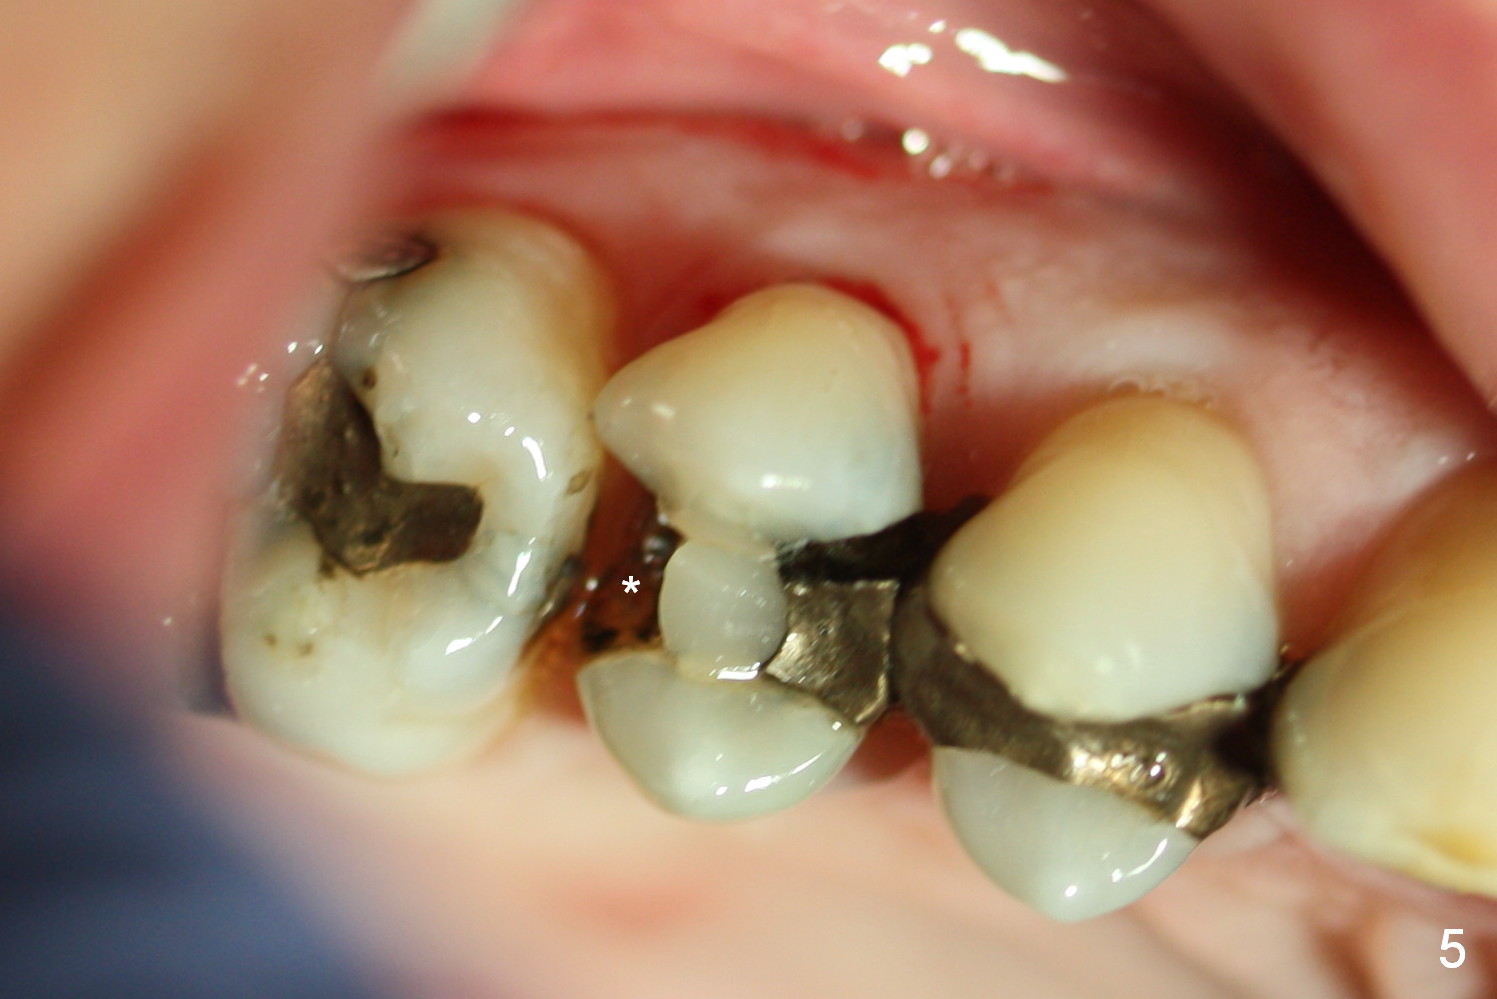

A 55-year-old man had 2nd caries with pulpitis at the tooth #4 a year ago (Fig.1), requiring RCT (Fig.2). The tooth fractured biting on a piece of nut shell inside a moon cake recently (Fig.3 *, 5, 6). There is a sinus septum apical to the apex of the affected tooth (Fig.1-3 arrowheads). After extraction and Metronidazole socket treatment, an immediate implant can be inserted into the septum for primary stability (Fig.4). The diameter of the implant will be decided by the measurement of the mesiodistal width of the root. Magic Expander (ME 3.0 mm) will be used to initiate osteotomy by going deep 4 mm, followed by ME 3.3 mm). If there is resistance to the 1st ME, use 1.6 mm drill. Allograft will be pushed upward with ME 3.3 mm prior to implant placement. Or try to insert (without tapping) ME 4.8 mm as deep as possible, hopefully with stability, and take PA. Place a larger implant for primary stability (4.5x11 mm).